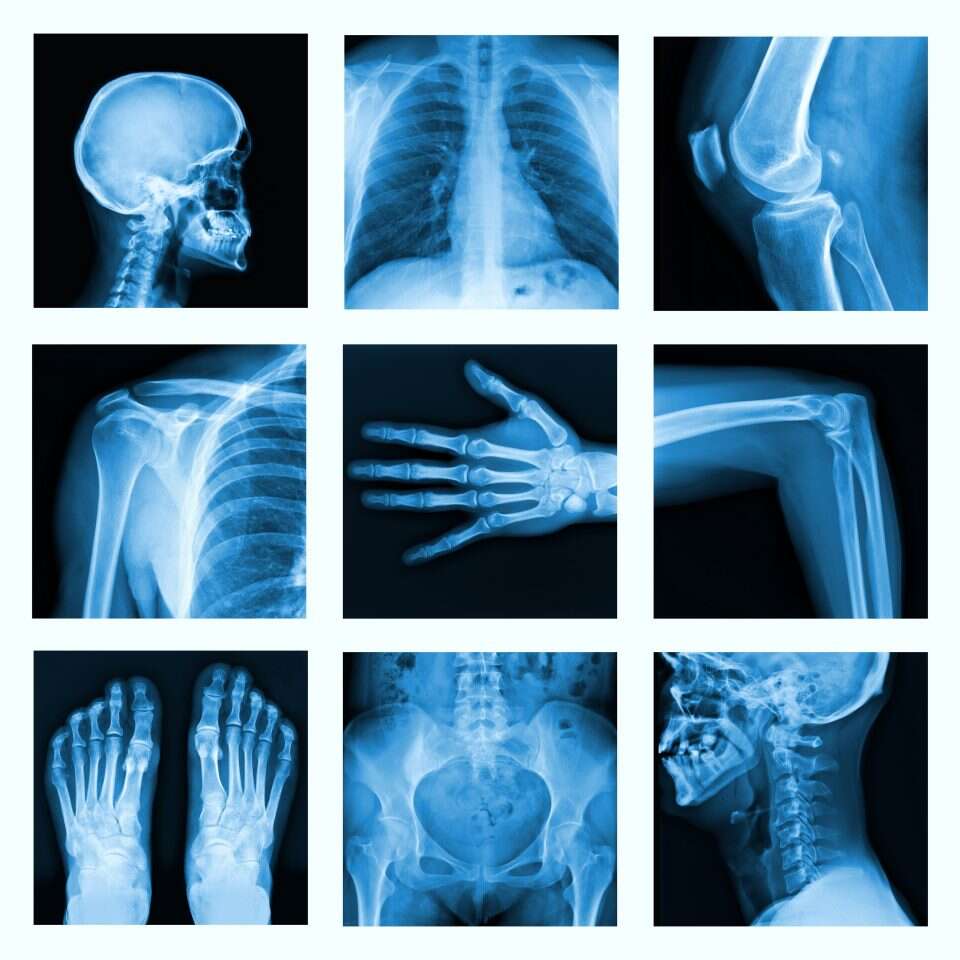

השמועה על הקרניים בוחנות הכליות והלב נפוצה לכל עבר. הציוד הנחוץ כדי להפיק אותן היה בר־השגה, ותוך זמן קצר עולם הרפואה למד את סגולות הגילוי. כבר באותה שנה נפתחה מחלקה לרדיולוגיה בבית חולים בגלזגו. מק אינטייר היה הראשון שאיתר בעזרת קרני רנטגן, בקיץ 1896, אבן בכליה. היכולת לאבחן באמצעותן מחלות ופתולוגיות הפכה אותן לכלי רפואי מרכזי, אבל לא רק העולם הרפואי הגיב בהתפעלות. במקביל לפרסום מאמרו של רנטגן בשני כתבי־עת מדעיים יוקרתיים בשפה האנגלית, Science ו־Nature, קיבל הציבור את הידיעה החדשותית גם בעיתונות הכללית. רבים נסחפו אחר ההתלהבות, אחרים הרימו גבה או התעלמו. רנטגנולוג בריטי סיפר כעבור שנים איך הגיב אביו כשקרא את העיתון היומי: "זו באמת שטות. איש אחד טוען שהוא גילה מין קרני אור שחודרות דרך חומר מוצק ומאפשרות לראות עצמות מבעד ליד. לאן כל זה יוביל אותנו? קרוב לוודאי שלא נשמע יותר על העניין, והדבר יישכח כאשר מישהו אחר ימציא פטנט לטיסה באוויר".

אבל הדבר לא נשכח. רנטגן שכלל את השפופרת כך שתצלם צלעות, חוליות וגולגולות, והציבור הרחב מצא שימושים משלו לתגלית החדשה. אולפני סטודיו נפתחו כדי לייצר "דיוקני עצם" לכל המעוניין. בחנות הכולבו בלומינגדייל'ס בניו־יורק עמד דוגמן שהראה בכל יום לעוברים והשבים את פעולת המכשיר החדש על גופו. פואמות, סיפורי בלשים ופרסומות שילבו את הקרניים חודרות הגוף כמוטיב בעלילה, ובלונדון נמכרו בגדים חסיני רנטגן, למעוניינים להגן על צניעותם. קריקטורות הציפו את העיתונים, חלקן משועשעות מאוד מהעניין. באחת נראה צלם המנחה את האדם הניצב מולו לחייך, כשלצידו התוצר: שלד מצחקק. בקריקטורה אחרת נראה בעל השולח את קרני האיקס אל דלת סגורה, כדי לבלוש אחר מעשיה של אשתו. שלישית הציגה מסיבת חוף "בסגנון רנטגן", ובה שורת שלדים מרקדים להנאתם. בינתיים ארגן תומס אדיסון תערוכה גדולה של קרני האיקס במסגרת תערוכת החשמל בניו־יורק, ושקד על פיתוח מכשיר רנטגן נישא.

קרני הרנטגן לא שינו את פני הרפואה לבדה; הן סייעו לעולם המדע במקומות רבים ובלתי צפויים. מכשירי רנטגן משמשים כיום לאיתור סדקים במבנים ובמטוסים, ולבדיקות ביטחון בשדות תעופה. בתחום הקריסטלוגרפיה, חקר הגבישים, הטכנולוגיה הזו מאפשרת לפענח את מבנה הגביש. בדיקת הסי־טי - שמבוססת על קרני רנטגן, וזיכתה גם היא את מפתחיה בפרס נובל - משרתת היטב את הארכיאולוגים. על דפי מוסף זה תיארתי לפני כמה שנים איך הובל אלכס, המומיה היחידה בישראל, לבדיקת סי־טי בבית החולים כרמל בחיפה. המומיה, שמתגוררת בדרך כלל במכון האפיפיורי למקרא, נלקחה למקצה שיפוצים לקראת תערוכה, ומכשיר הסי־טי אפשר לדעת מה מצבה. הסריקה הראתה שבר ברגל וסדק בתכריך, וכך ידעו המשחזרים מה לשקם ואיך לטפל. סריקה כזו, לצד בדיקות אחרות, מאפשרת גם למדע הרפואה להפיק המון ידע מהמתים הקדומים על החיים כיום. אגב, לפני חמש שנים סיפקה בדיקת סי־טי הפתעה לחוקרים הולנדים: הם הכניסו למכשיר הדימות פסל בודהה בתנוחת המדיטציה המוכרת, ונדהמו לגלות בתוכו את גופתו החנוטה של המורה הרוחני הסיני ליקוון, שמת לפני כאלף שנה.